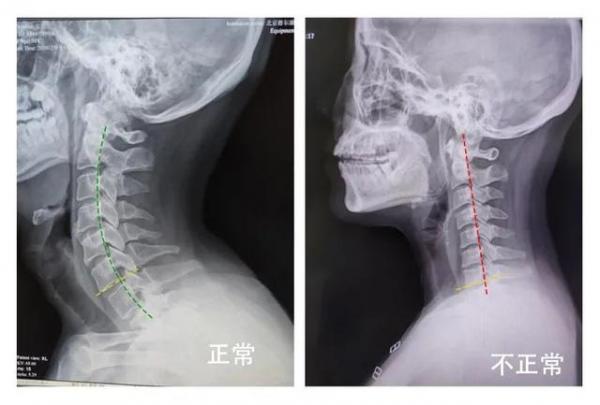

颈椎是一个精巧的弧形结构,它支撑着头部,分散着颈部和头部的压力。颈椎生理曲度是颈椎保持正常功能和稳定性的关键。然而,久坐不动、长时间低头等不良姿势,就像一把无形的刻刀,逐渐消磨着这个重要的生理曲度。